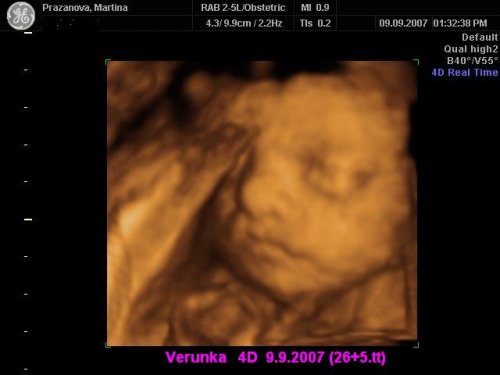

Už se nemůžeme dočkat 1.5....jdeme na 4D UTZ, tak doufám, že se nám ten náš klučík ukáže v plné své kráse 🙂))